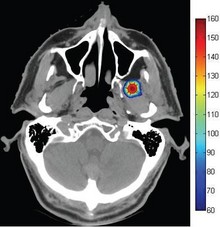

We present an optimization procedure to improve the propagation properties of the depressed-cladding, buried micro-structured waveguides formed in a z-cut lithium niobate (LN) crystal by high repetition rate femtosecond (fs) laser writing. It is shown that the propagation wavelength ... En savoir plus